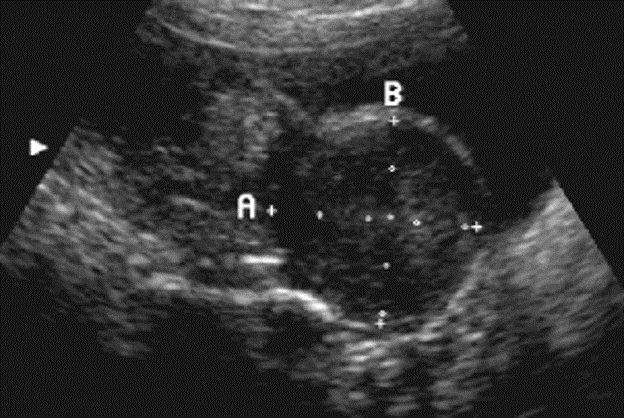

Pic shows large uterine fibroids

Firboid in pic is indicated